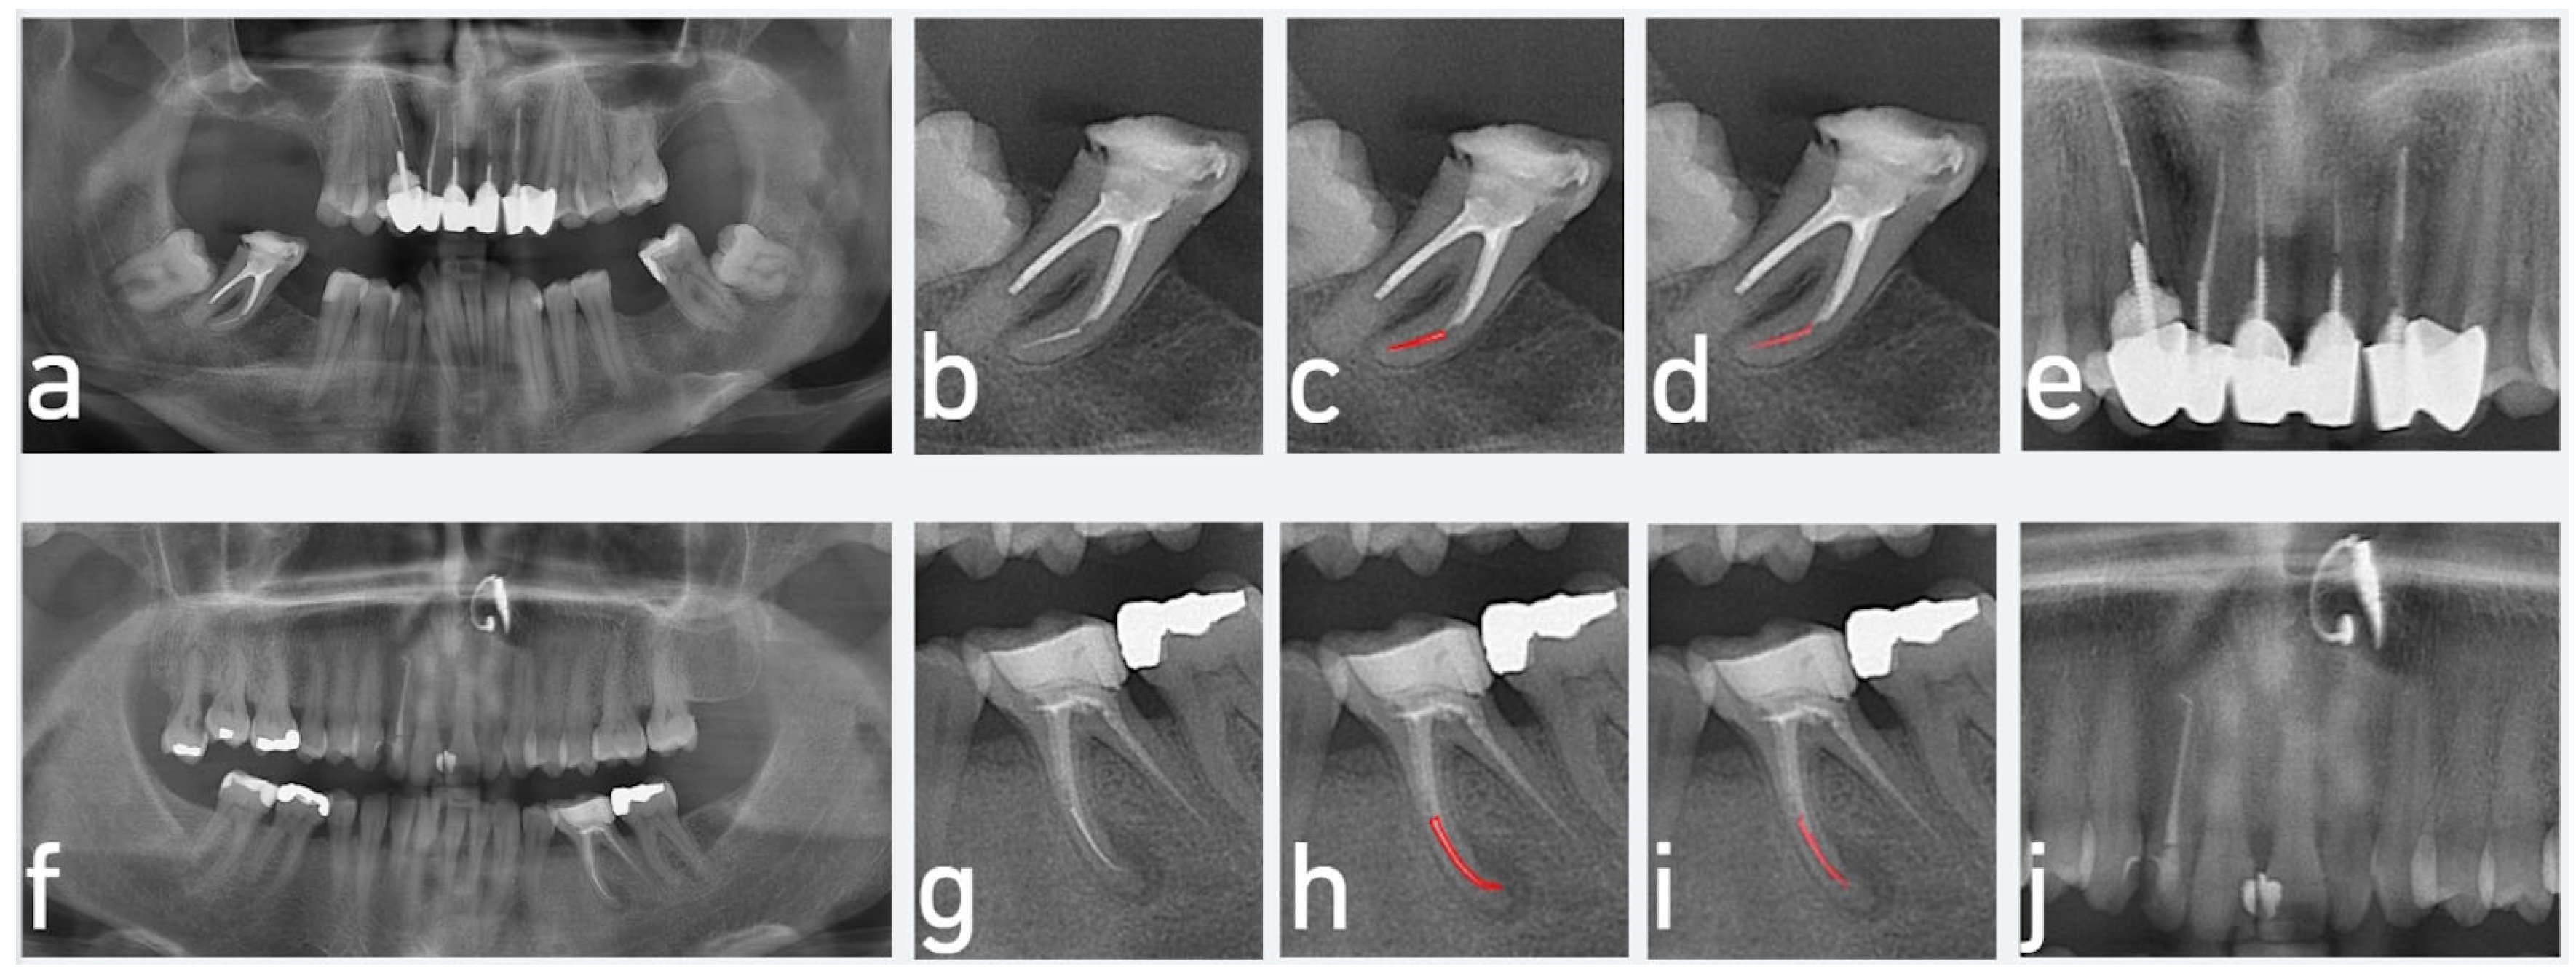

2.1. Data Preparation and Labelling